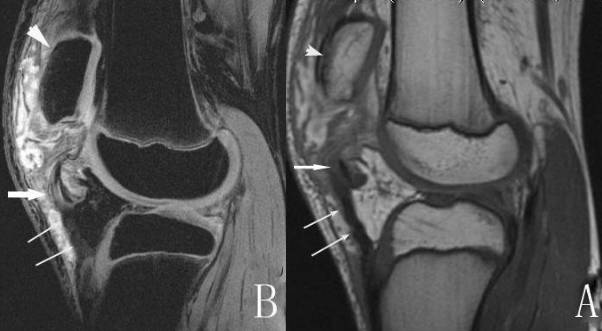

以内侧副韧带损伤(MCL)为例,可分为Ⅲ级

Ⅰ级:MCL 扭伤,可有水肿及出血;MRI 表现为损伤区T1WI 低信号,T2WI、STIR 呈高信号,在亚急性期出血时T1WI 可显示为高信号;而MCL的形态并不发生改变,与周围组织有明显的分界,冠状面上表现为平行于骨皮质的带状低信号影。

Ⅱ级:MCL 部分撕裂;Ⅱ级损伤,因韧带部分撕裂,水肿和出血使韧带和周围组织分界不清,其韧带可有移位,不再平行于骨皮质缘,部分纤维断裂处在T2WI 或STIR 上呈高信号。

Ⅲ级:MCL 完全断裂。Ⅲ级损伤,因韧带完全撕裂,使其连续性中断,并伴有韧带的增粗肿胀,整条韧带结构与肌肉信号混合,界限消失,不能辨认其结构走形,在T2WI 或STIR 上呈弥漫性高信号,有时韧带断端呈波浪状改变,关节囊内可见不等量的积液影像